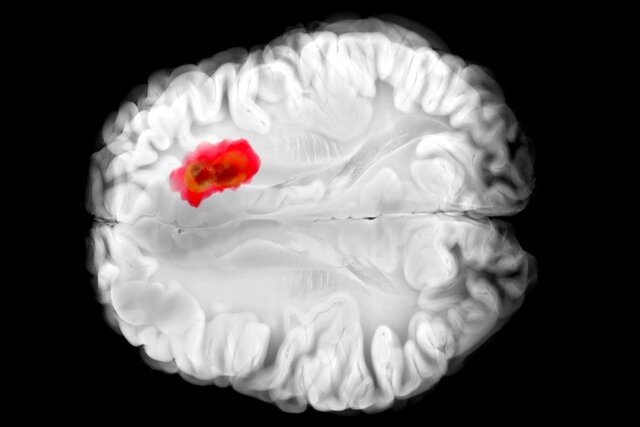

تصور میشود که همین آنزیم در سرطانهای مغزی گلیوبلاستومای تهاجمی نقش دارد. این درک جدید از «هیدرالازین» میتواند راه را برای درمانهای جدید سرطان هموار کند و همچنین اثربخشی دارو را برای اهداف فعلی آن بهبود بخشد.

مطالعات قبلی نشان دادهاند که تومورهای گلیوبلاستوما اغلب سرشار از ADO هستند و آن را برای تولید ماده شیمیایی به نام هیپوتائورین(hypotaurine) میربایند که به سلولهای سرطانی کمک میکند تا گسترش یابند، برای مدت طولانیتری زنده بمانند و فشار را تحمل کنند.

در آزمایشهایی که با سلولهای گلیوبلاستومای انسانی انجام شد، «هیدرالازین» با مسدود کردن ADO رشد تومور را متوقف کرد.